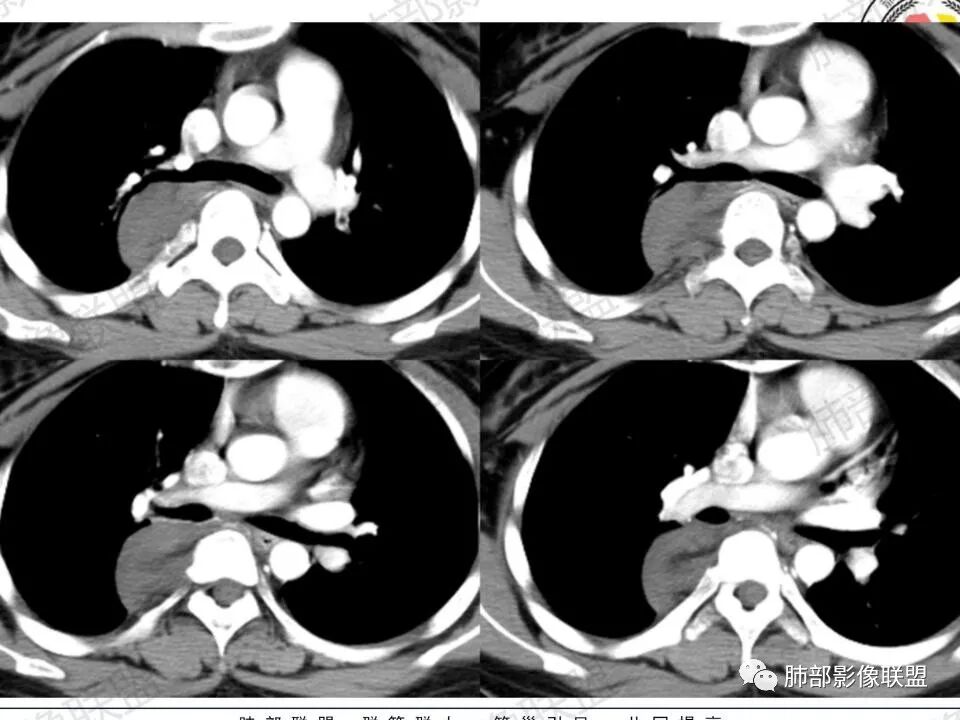

(3)增強:

后纵隔神经节细胞瘤常动脉期无明显強化、或轻度间隔、包膜或瘤体强化,延迟期可进一步斑片、结节状轻度或中度强化,强化程度进行增加,呈渐进性延迟强化,但強化程度一般为轻度到中度强化,究其原因可能是神经节细胞瘤瘤体内含有大量黏液基质和胶原纤维,使得细胞外间隙扩大,阻碍了对比剂的灌注,从而延缓了对比剂的积累,因此其动脉期多无明显强化或仅有轻度强化,延迟期呈渐进性轻度强化是后纵隔神经节细胞瘤强化特征。大部分病灶有轻度-中度强化,部分病灶无强化,这还可能与瘤组织内部间质血管含量多少相关,无强化病例瘤组织内部主要由胶质纤维和节细胞组成,间质血管较少,因此强化较低,而强化程度较高的病理可见较多的扩张、充血的毛细血管,引起较多的对比剂积蓄,因此强化相对明显。因此,神经节细胞瘤极少出现瘤组织早期强化,而多呈延长渐进性强化,增强扫描神经节细胞瘤内细胞成分可增强,黏液基质不强化。

3.块影血供动脉来自肋间动脉,且由内后方侧入,其与下腔静脉之间未见回流通道。血管未见破坏,相邻组织未见侵入。

5.轻度渐进性强化。